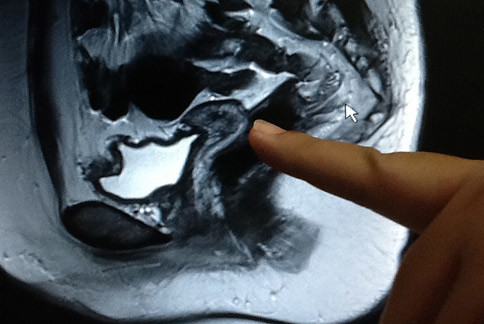

子宮...